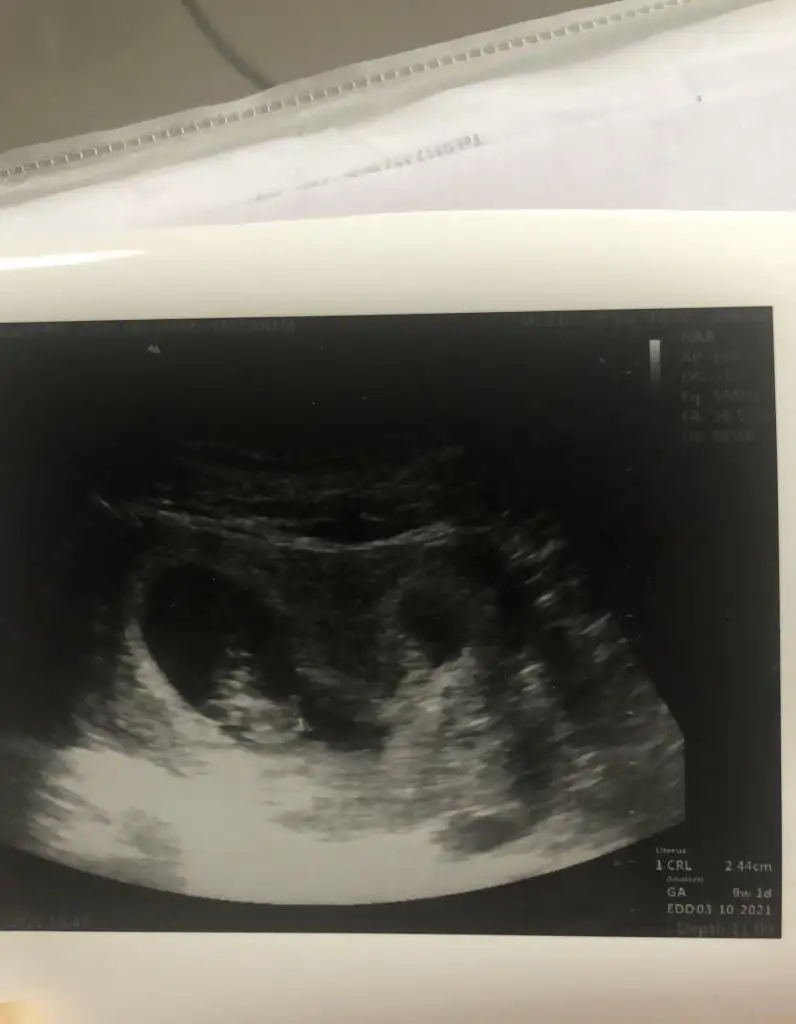

Kızlar herkese selam:) Bugün benim de kontrolüm vardı normalde 11. Haftadayız 12+3 çıktı, gidene kadar doğru dürüst bir şey hissetmiyordum yani bulantılar, ikinci çocuk nasıl olacak endişeleri fln sarmıştı.. ama bugün ultrasonda öyle net gördük ki kıpır kıpır hareketliydi parmaklarına kadar görebildik:) cinsiyeti göremedim dedi ya da görüp söylemedi bilmiyorum, ikili için ölçüm yapıldı üzerine hastaneye gidip kan verdim orada da muayene oldum kan verebilmek için erkeğe benzettim ben dedi... bir oğlum var gönül ister ki ikinci kız olsun ama yeter ki sağlıklı olsunlar zaten öğrenene kadar sürüyor bu heyecan öğrendikten sonra hepsi bir :) Bizden haberler böyle dilerim güzel haberler aldığımız bir hafta olur hepimizin